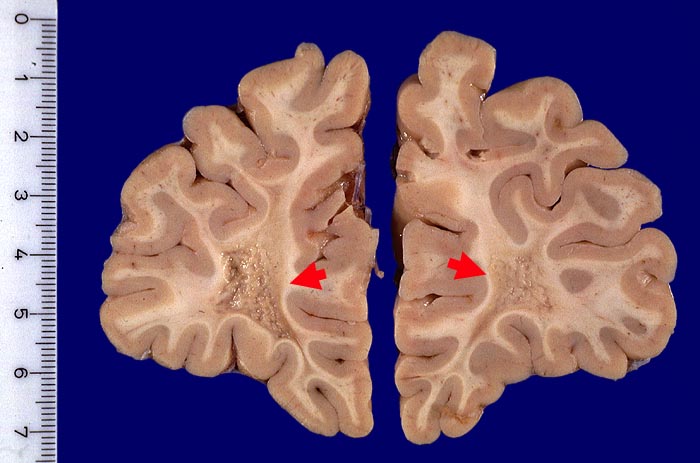

PathoPic – image database / PathoPic ID 2050 - Alte Entmarkungsherde frontoorbital beidseits

Alte Entmarkungsherde frontoorbital beidseits

Grau verfärbte und eingesunkene Areale mit granulärer Oberfläche im frontalen Marklager beidseits.

Alte Entmarkungsherde (Dm 1,5cm) der frontoorbitalen Marksubstanz links und des Balkenknies (Dm 0,5cm): teilweise wiederbemarkte nicht aktive Multiple Sklerose Herde

Keine Symptomatik bekannt. Sogenannte silent multiple sclerosis.